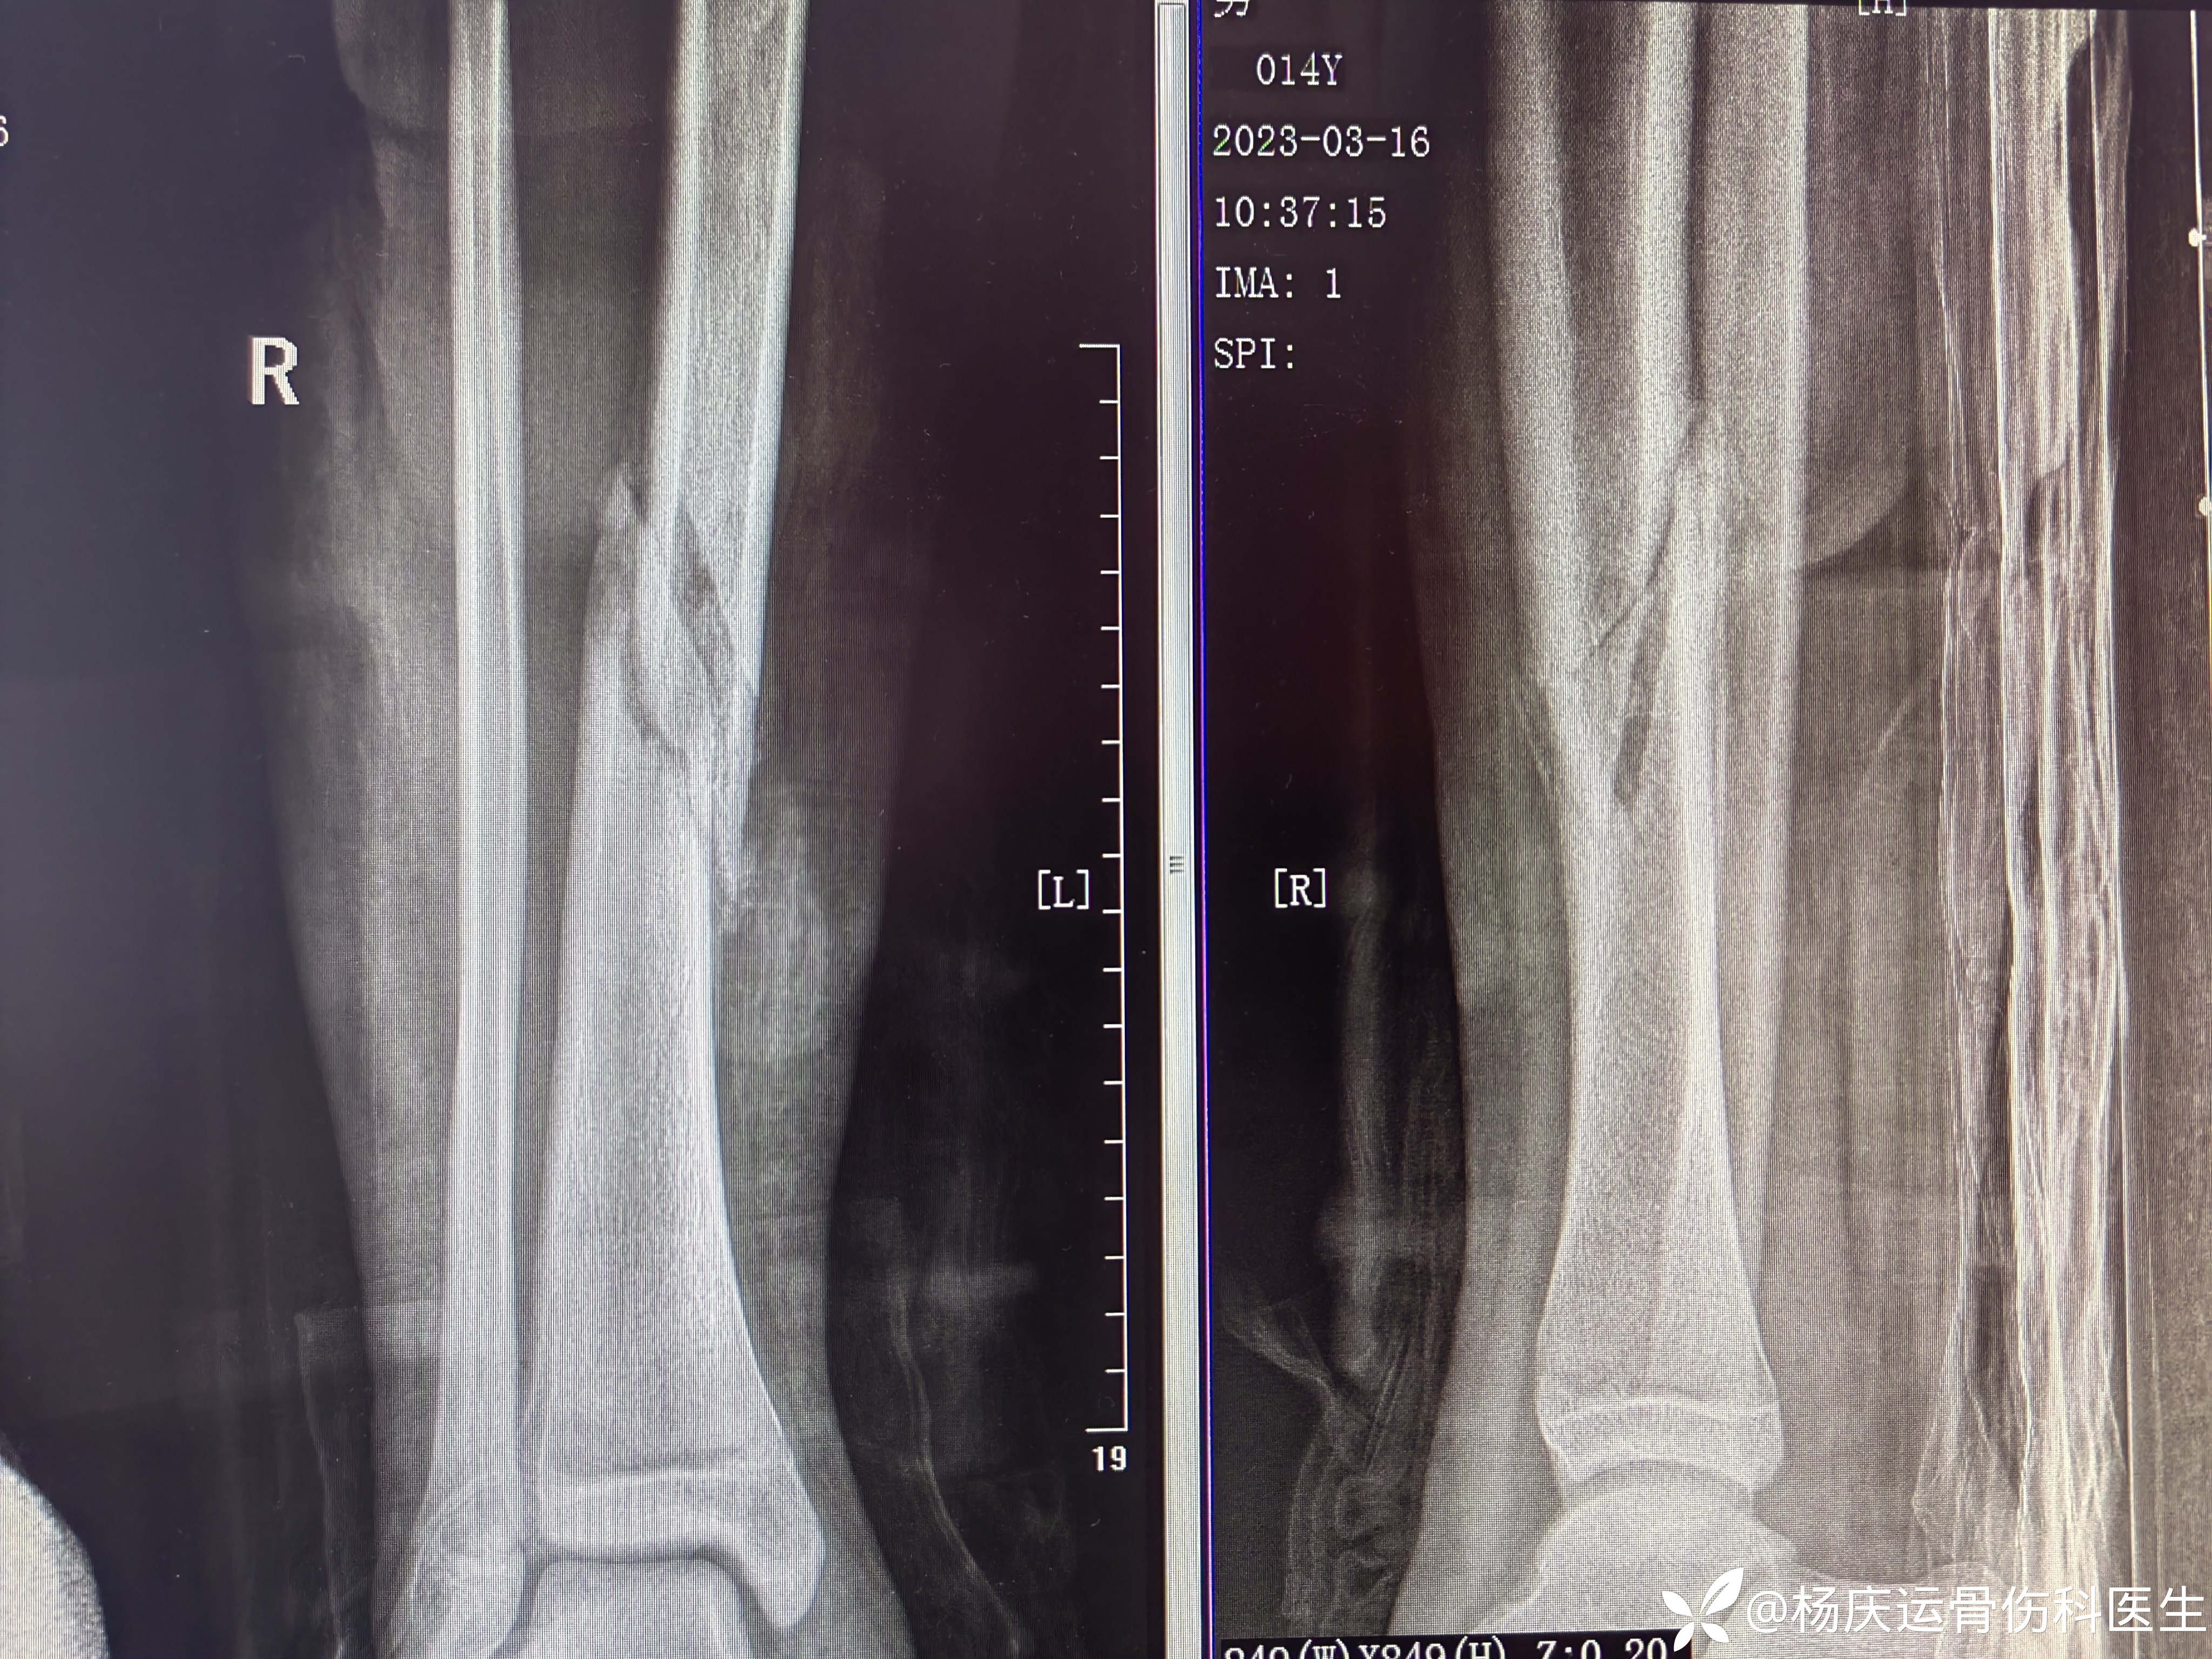

近2个月复查